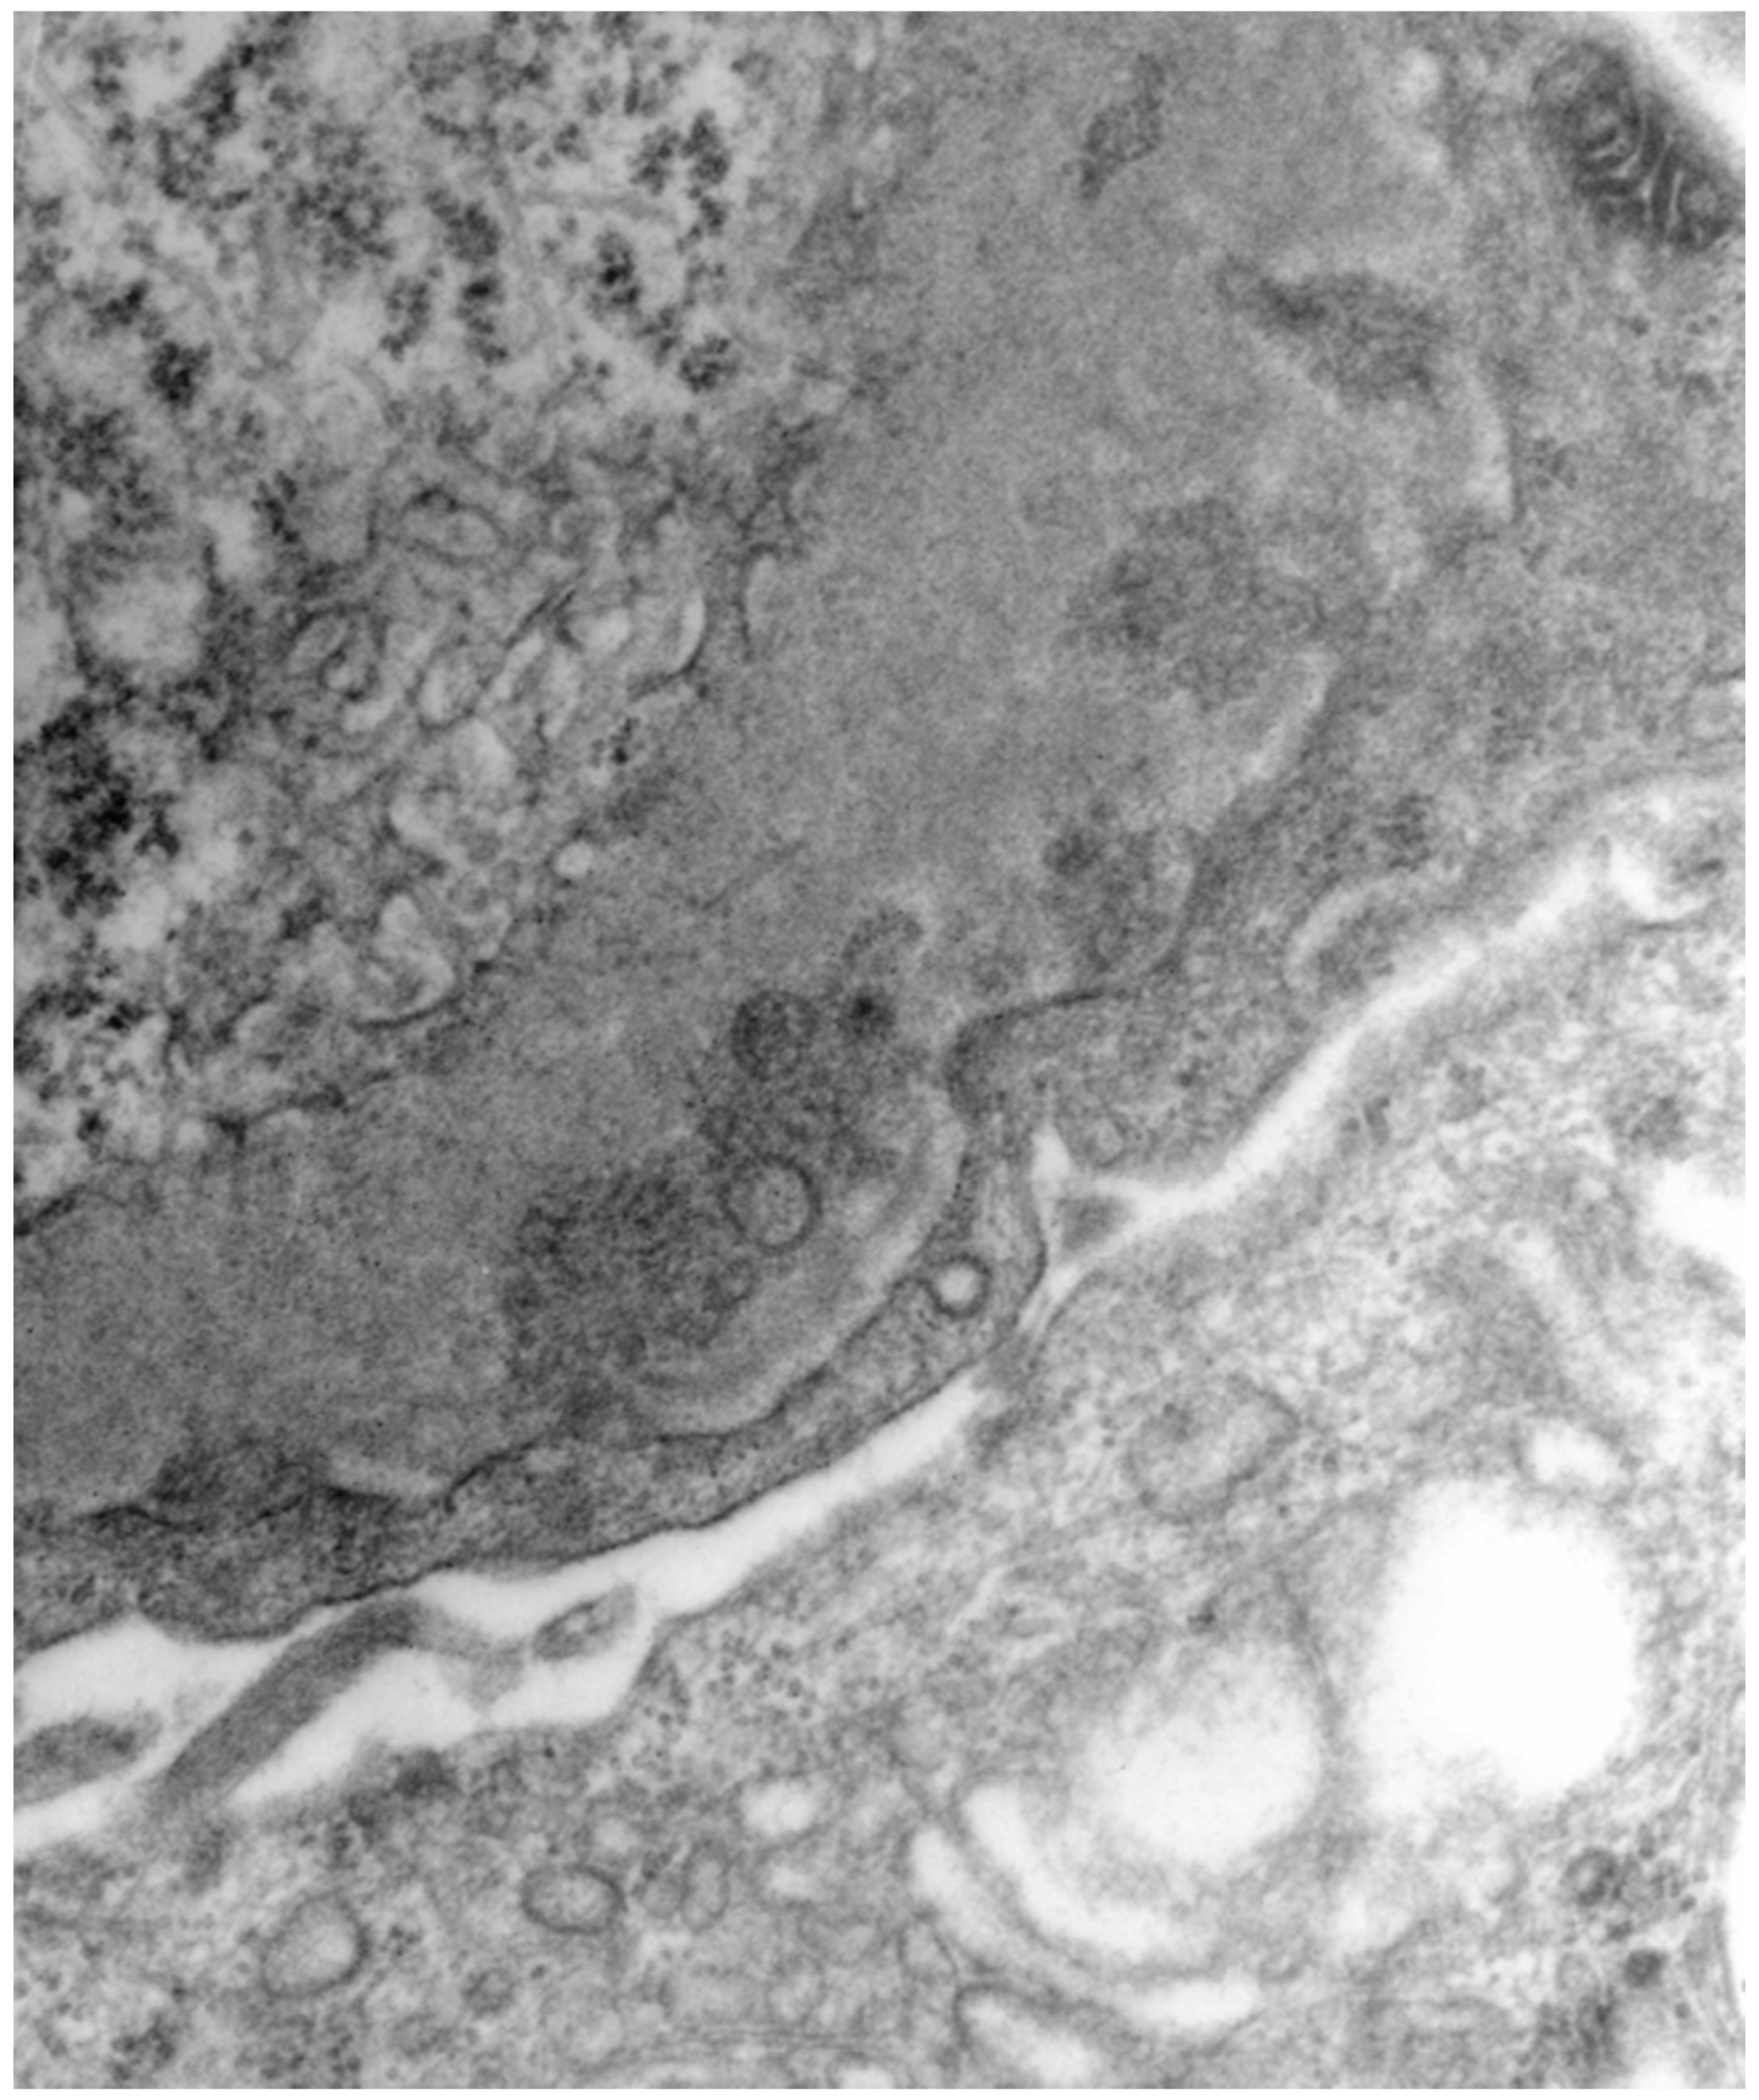

3.2. HBV-Related Membranoproliferative Glomerulonephritis (MPGN)

- Li, C.; Li, H.; Su, W.; Wen, Y.B.; Ye, W.; Ye, W.L.; Cai, J.F.; Qin, X.Z.; Li, X.M.; Li, X.W. Clinicopathological study of mixed cryoglobulinemic glomerulonephritis secondary to hepatitis B virus infection. BMC Nephrol. 2020, 21, 395. [Google Scholar] [CrossRef] [PubMed]